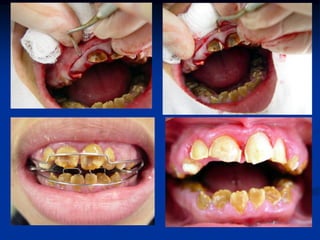

   Odontologia Estética e Cosmética

   Ortodontia

ORTODONTIA e ORTOPEDIA

>Pequenos

Movimentos

>Reabilitação

Ortodôntica

Preventiva / Interceptativa / Ortopédica